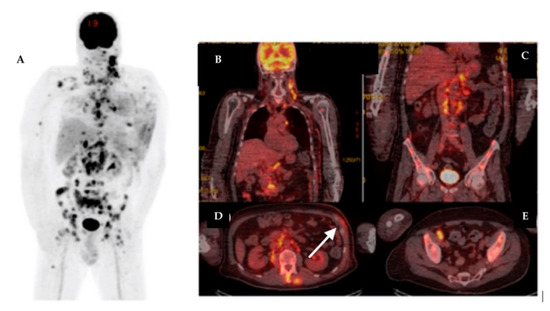

| 17 | 61 | IDC | RM + ALND | Yes | Yes | IIIB | LN | LN, Lu, M, Bn | 3.1 | Hodgkin Lymphoma | 11.6 |

| 21 | 61 | IDC | RM + ALND | Yes | Yes | IIC | LN | – | 2.38 | Thyroid cancer | 23.1 |